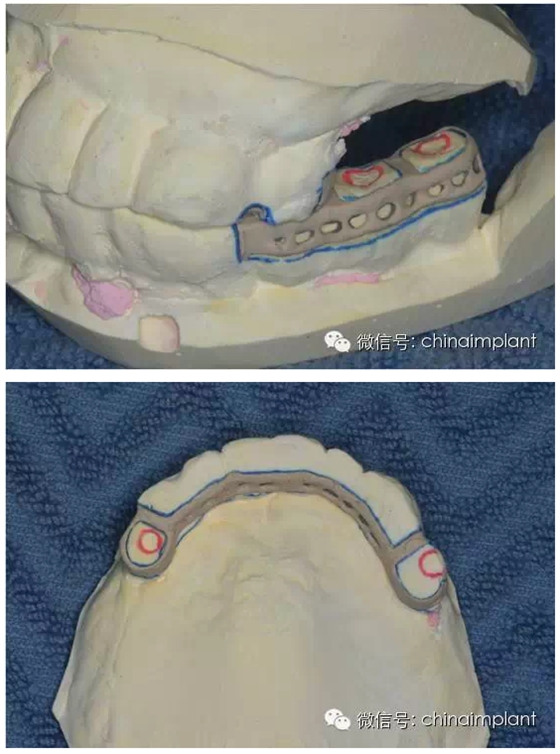

之前針對全口無牙進(jìn)行種植修復(fù)的案例中,因?yàn)轭M骨的原因,后期使用橋冠修復(fù)時(shí),一般是3部分(兩側(cè),磨牙,前牙),最近的案例中修復(fù)是一般都是做一體式的橋冠,現(xiàn)在從臨床的修復(fù)案例來看,沒有什么問題。

之前的時(shí)候,使用圓錐形基臺,但是附著的力量容易分散。(最近由于費(fèi)用的問題多使用UCLA形態(tài)的基臺)